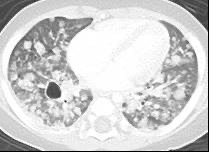

肺病変

成人では肺だけに病変がある患者さんがあり、検診などでたまたま見つかることがあります。成人の患者さんのほとんどは喫煙者です。子どもでは、ほとんどが多臓器型で肺が病変のみという患者さんはありません。自覚症状としては、乾いた咳、息切れ、息苦しさです。肺が破壊されると、肺が空気のふくろにおきかわり、それが破れると、肺と胸の壁の間に空気が漏れて肺が縮んでしまう、すなわち気胸をおこします。さらに肺の破壊が進むと、空気のふくろだらけ、すなわち蜂巣様肺となり、息ができなくなることがあります。